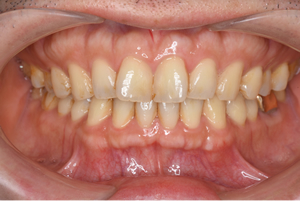

81歳、上下精密義歯

院長(46歳、欠損なし)

*ほぼ同じ値ですが、 上下精密義歯装着者の方が、私より高い数値が出ています!!